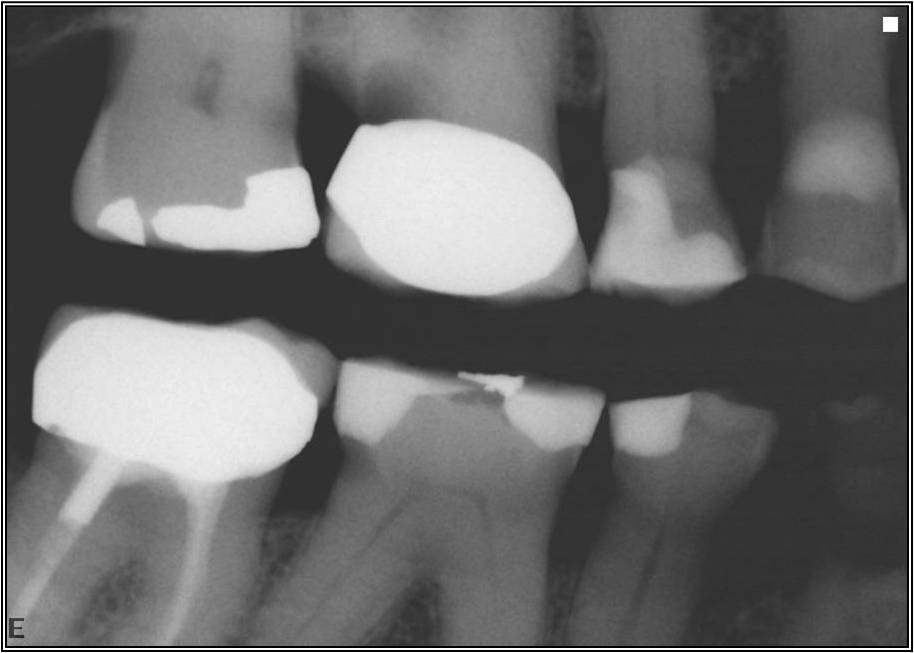

Excellent diagnosis essentially begins with two fundamental components: a doctor willing to listen to the patient’s chief complaint, and proper diagnostic tools. Among the most important tools are a precise periapical radiograph (PA) and bitewing (BW). Although a PA is often enough to provide an accurate portrayal of the patient’s condition, sometimes it alone does not suffice. Figure 1, Figure 2, and Figure 3 demonstrate a case that illustrates this point clearly. Despite two acceptable PAs (Figure 1 and Figure 2), it is difficult to assess the source of the patient’s pain to temperature. However, the BW radiograph Figure 3 provides significantly more clarity than either of the two PAs. The BW depicts localized bone loss (around tooth No. 2), a pulp stone (No. 2), a flat occlusion, numerous calcified canals, multiple restorations in tooth No. 30, and gross decay especially on tooth No. 3, which is the source of the patient’s pain to temperature. In this instance these images depict how much more useful a BW can be than just a conventional PA.